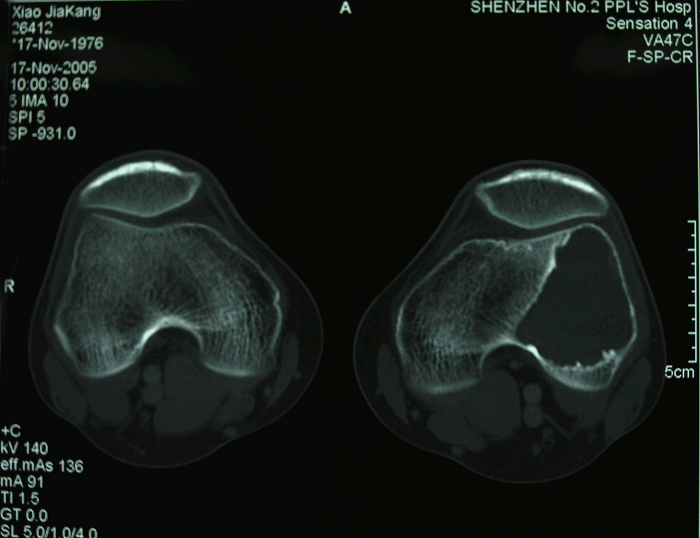

2.CT与MRI表现

CT检查对肿瘤破坏或穿破骨皮质、侵犯关节内可提供更为准确的评估。MRI成像在评价肿瘤在骨内扩展程度以及软组织和关节内受累范围有重要价值。骨巨细胞肿瘤在T1加权像中典型的改变为低到中等信号,而在T2加权像中显示中等到高信号,由于病变内存在大量的含铁血黄素,所以在上述两种MRI表现中经常产生低信号改变。

图 2、3、4 术前CT

图 10、11 术前CT